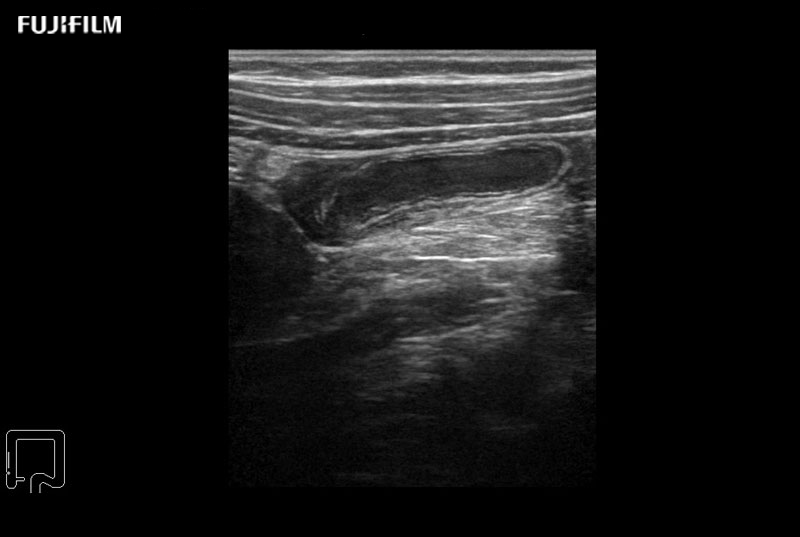

Use of trapezoid mode with a linear transducer extends the width of the field of view permitting a greater understanding of the orientation and size of the target and its surroundings.